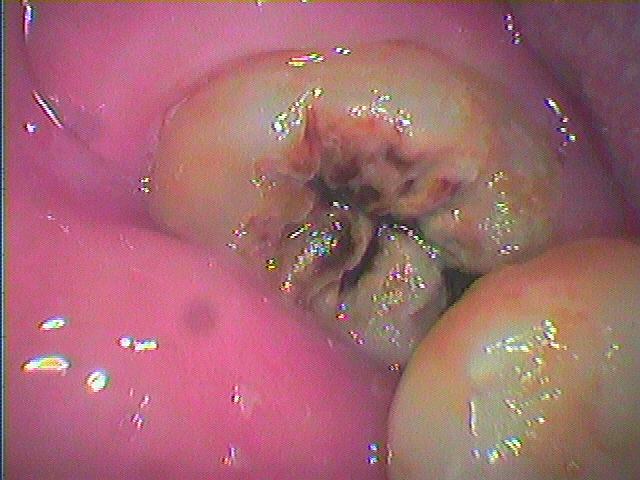

右下親知らずの埋伏歯の抜歯 これを抜かなければ右下7番遠心部のカリエスが治療できません|お知らせ |広島市安佐南区の歯科医院 右下親知らずの埋伏歯の抜歯 これを抜かなければ右下7番遠心部のカリエスが治療できません トップ お知らせ・ブログ お知らせ 右下親知らずの埋伏歯の抜歯 これを抜かなければ右下7番遠心部のカリエスが治療できません 右下親知らずの埋伏歯の抜歯 これを抜かなければ右下7番遠心部のカリエスが治療できません 親知らずもひどく虫歯になっています このように虫歯になっています 周囲炎にもなってきています このように骨吸収が起きています 抜歯しました 切開もしていないです 抜歯しましたが、 7の遠心部に虫歯がありました 縫合して終了です Web診療予約 初めての方へ 選ばれ続ける理由 院内設備について 歯が痛いしみる一般歯科 歯がぐらぐらする歯周病 健康な歯を保ちたい予防歯科 子供の虫歯予防をしたい小児歯科 銀歯をセラミックに審美歯科 白い歯を目指しませんか?ホワイトニング 矯正専門医がいるので安心矯正歯科 抜けた歯を補いたいインプラント・入れ歯 医院案内 スタッフ紹介 メリィハウス歯科クリニックオフィシャルホームページ ラベンダー歯科クリニックオフィシャルホームページ お知らせ・ブログ ホーム 診療科目 一般歯科 歯周病治療 予防治療 小児歯科 審美治療 ホワイトニング 矯正歯科 入れ歯・インプラント マウスピース矯正 初めての方へ 院長・スタッフ 設備紹介 医院案内・アクセス メニューを閉じる